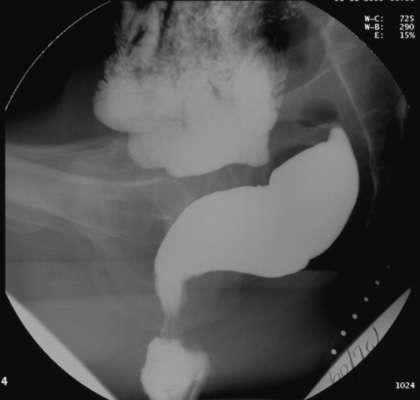

place the patient in the sitting position on the Brunswick Chair mounted

on the footrest of the upright fluoroscopic table. The entire

examination is performed with the patient seated in the right lateral

projection.

Position the fluoroscope so that the field of view includes the

sacrum posteriorly, the symphysis pubis anteriorly, and an area about

two inches below the skin surface of the perineum (to allow for downward

descent during evacuation). Also include the commode's centimeter marker

within the field of view to permit later measurement corrections for

magnification.

in the resting state